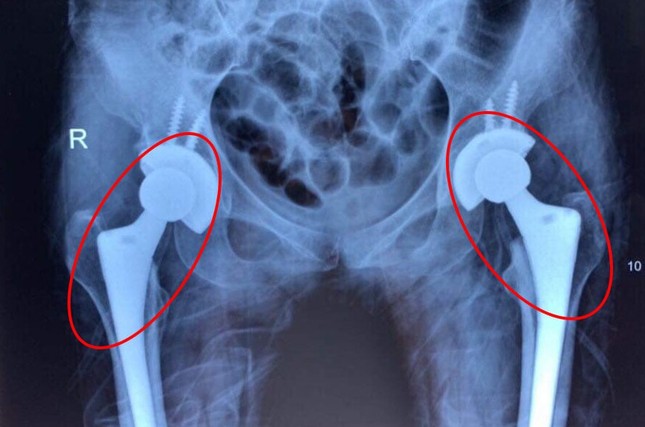

Nhiều bệnh nhân còn rất trẻ nhưng đã phải thay cả 2 khớp háng do bị mục xương |

Trước đây, bệnh nhân bị mục khớp háng cả hai bên thường phải thay từng khớp một. Hạn chế của kỹ thuật trên là khiến người bệnh chịu nhiều lần đau đớn khi phẫu thuật và phát sinh thêm nhiều khoản chi phí. Hiện nay, với những tiến bộ về chuyên môn và dụng cụ y khoa các bác sĩ có thể thay khớp háng cả 2 bên cho người bệnh trong cùng một cuộc mổ không chỉ giúp bệnh nhân tiết kiệm được chi phí mà còn giúp người bệnh nhanh chóng bình phục, cải thiện chất lượng cuộc sống cho người bệnh.

BS Lãm cho biết, trong số 10 ca bệnh đã thay 2 khớp háng tại Bệnh viện Hoàn Mỹ Sài Gòn, hầu hết là bệnh nhân trẻ tuổi, chỉ khoảng 2 đến 3 tháng sau ca mổ bệnh nhân đã có thể vận động bình thường trở lại. Tuy nhiên, khớp nhân tạo chỉ có thể sử dụng khoảng 25 đến 30 năm. Người trẻ tuổi thường phải mổ lại để thay khớp khác, việc phẫu thuật lần 2 là thách thức với các bác sĩ và người bệnh bởi nguy cơ tai biến, biến chứng ở mức cao.